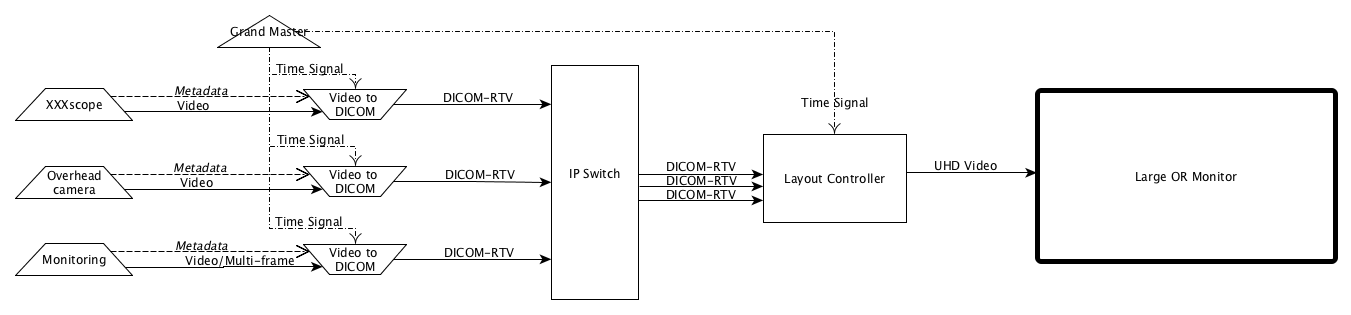

- PPPP.7. Example of DICOM Real-Time Video Implementation

- PPPP.8. Storage Considerationa

- PPPP.9. Example of Engineering Implementation